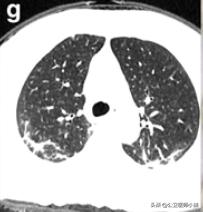

肺部感染涉及多个肺叶-1

肺部感染涉及多个肺叶-2

肺部感染涉及多个肺叶-3

当涉及到一个或多个肺叶,肺功能的影响并不严重时,呼吸急促和呼吸困难的症状也并不严重。随着病情的发展,肺部实变开始吸收,密度降低逐渐变成毛玻璃样的混浊,像融化的糖。